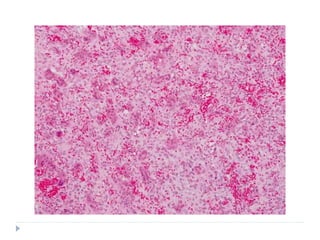

 At low power magnification: STARRY SKY PATTERN

is often appreciated

HISTOPATHOLOGY

 STARRY SKY PATTERN

 Phenomenon that is caused by the presence of

macrophages within the tumour tissue

 Macrophages have abundant cytoplasm which

microscopically appears less stained in comparison with

the surrounding cells

 These macrophages also contain phagocytic debris

 THE MACROPHAGES THUS, STAND OUT AS STARS

SET AGAINST THE NIGHT SKY OF DEEPLY

HYPERCHROMATIC NEOPLASTIC LYMPHOID CELLS